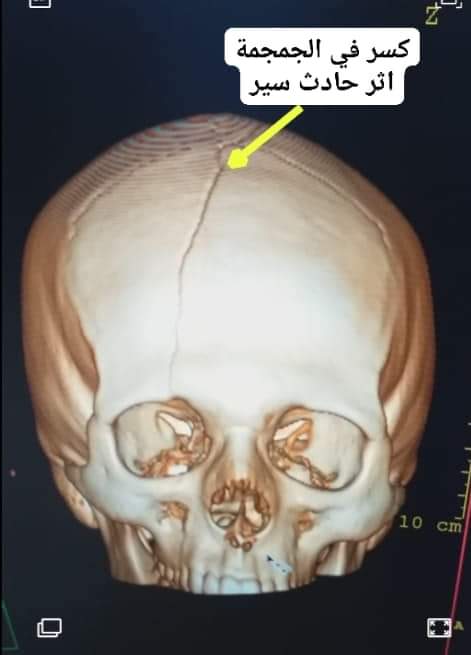

كسر في الجمجمة اثر حادث سير